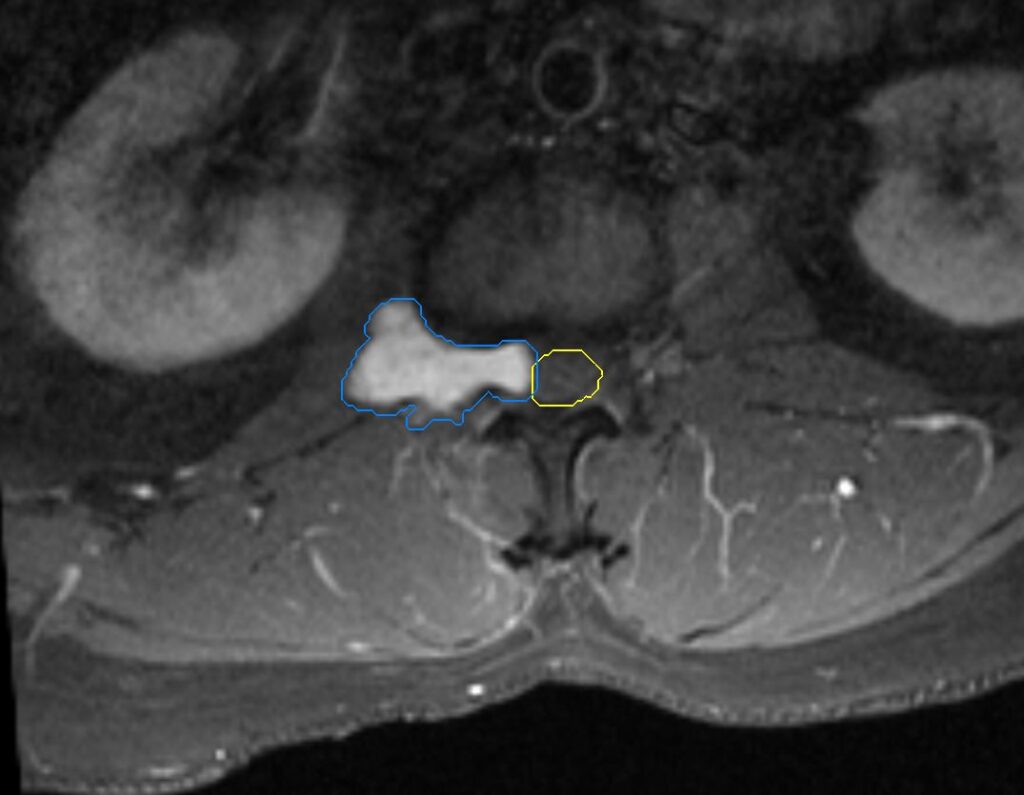

MRI: Lesion compatible with a paraspinal meningioma measuring 4.1cm at the level of L1-L2

Planning CT Images